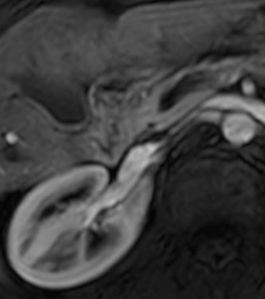

Aspetti RM: minuto nodulo della testa pancreatica ipointenso in T1.

image